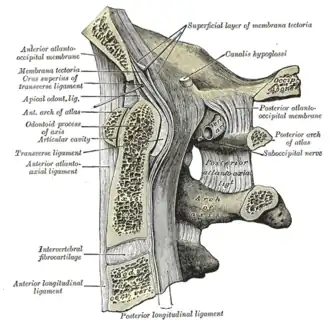

Median sagittal section through the occipital bone and first three cervical vertebrae

Median sagittal section through the occipital bone and first three cervical vertebrae -